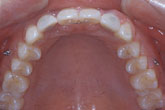

15세 7개월 된 남학생이 상악전치부 spacing을 주소로 내원하였다. 방사선사진을 촬영하고 상·하악 인상을 채득한 후 통상적인 방법으로 교정진단을 한 결과 다음과 같은 problem을 갖는 것으로 진단되었다 (그림 1,2).

그림 2. 내원시 측모두부방사선사진과 파노라마 사진을 통해 결손부위에 인접한 치아들의 위치를 파악할 수 있다.

측모두부방사선규격사진에서는 상악골이 다소 돌출되어 있는 양상을 보이고 있는 것 외에는 두드러진 문제가 보이지 않았다. 파노라마 사진에서 상악중철치의 치근이 짧은 것이 눈에 띄었으며 좌우 견치가, 특히 좌측 견치가 견치위치라기보다는 측절치 위치에 자리잡은 것으로 나타났다. 석고모형 분석 결과 상악의 공간 양은 약 16mm로 측정되었으며 개개 치아크기를 평균치와 비교시 상악 양 중철치가 두드러지게 작은 것을 알 수 있었다. 반면 하악은 정상적인 배열을 보였다. 상·하악 교합 분석시 좌측은 정상적인 Cl I을 보였으나 하악 치열 정중선의 우측 편위와 함께 우측교합은 Cl II를 나타내었다. OB과 OJ은 3.0과 3.5mm로 정상보다 1.0 또는 1.5mm 큰 양상을 보였다 (그림 2,3).